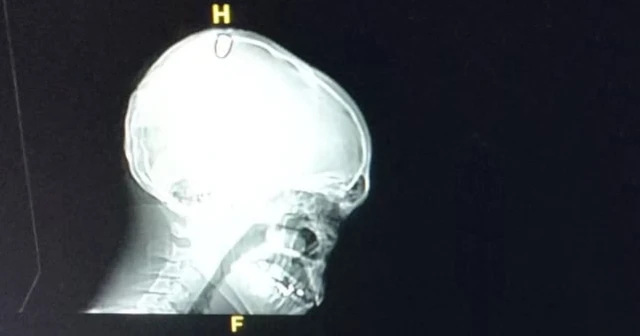

Gencin hastanede çekilen tomografisinde başındaki mermi çekirdeği görülürken, hayati tehlikesinin olmadığı öğrenildi. R.A., başındaki mermi çekirdeğinin çıkarılması için ameliyata alındı.